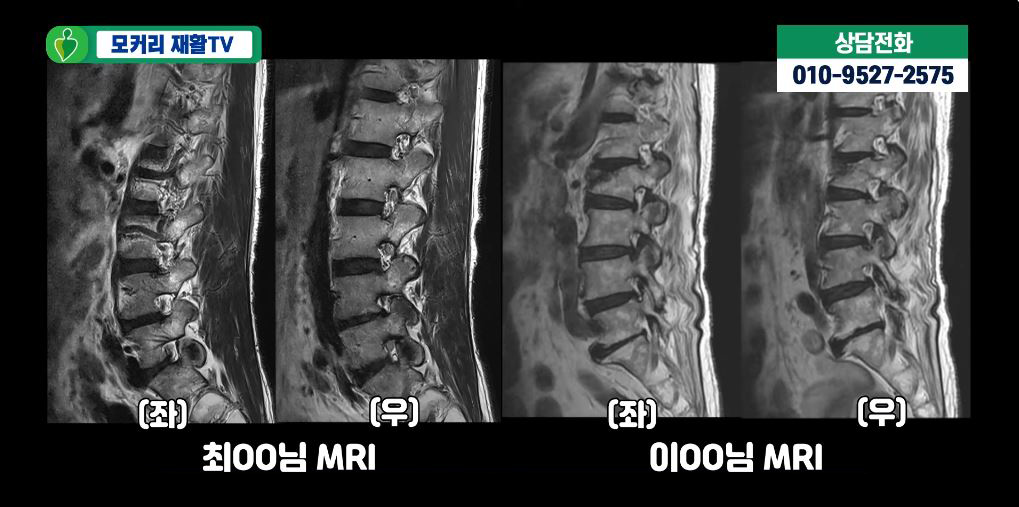

아래 사진은 실제 근감소증 환자들의 MRI입니다.

이 환자분들의 MRI를 보면 두분 다 60세 이상이시라 노화로 인해 MRI상으로 협착과 퇴행성디스크가 보입니다.

하지만 협착이 심하지 않아서 다리로 가는 신경을 누르는 것 같지는 않습니다. 이분들의 엉덩이나 다리증상이 협착증 증상이 아닐 가능성이 높은 것입니다. 그럼에도 불구하고 이분들처럼 MRI로 퇴행성디스크와 협착이 보이고 허리와 다리가 아프면 무조건 협착증이라고 진단하는 경우가 매우 많습니다. 이분들도 역시 협착과 퇴행성디스크 진단을 받았습니다. 하지만 이분들의 허리통증, 엉덩이통증, 다리증상과 걷는 게 힘든 증상은 협착과 퇴행성디스크 문제보다는 근감소증과 근육 뭉침 때문입니다.

보시다시피 두분 다 척추기립근도 지방화가 심하게 돼있고, 근감소증 검사에서도 양성반응을 보이셨습니다. 이렇듯 협착증이 아닌데 협착증으로 잘못 진단하게 되면 엉뚱한 치료를 받으면서 시간만 낭비하고, 또 고생은 고생대로 하면서 치료가 안 되는 그런 결과를 낳게 됩니다. 따라서 반드시 협착증과 근감소증을 잘 구별해야 하며, 최근에 유달리 근육이 많이 줄어들었고, 특히 허리가 아프고 구부러지며, 걸음걸이가 느려지면서 다리가 아픈 증상이 나타난다면 근감소증 검사를 받아볼 필요가 있습니다.